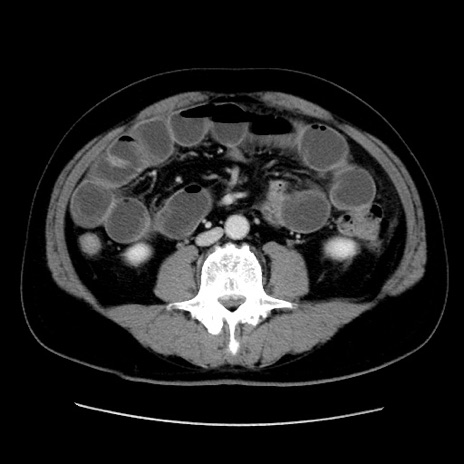

症例16(横断像)

【症例】 70歳代男性

【主訴】 腹痛、嘔吐

【現病歴】 約1ヶ月前より間欠的に腹痛と嘔吐あり、当院消化器内科を受診したところCTで多発する肝臓のLDAを指摘され、精査中であった。以降は消化器症状は安定していたが、2日前より嘔気と腹痛があり、同日より排便・排ガスが消失した。改善認めず、 本日、救急外来を受診した。

【既往歴】 大腸ポリープ切除後。

【身体所見】意識清明・会話良好、BT 36.3℃、BP 127/80mmHg、 P 80bpm、腹部:膨満あり、平坦・軟、上腹部正中および下腹部正中に圧痛あり、反跳痛なし、筋性防御なし。

【データ】WBC 7200、CRP 0.77